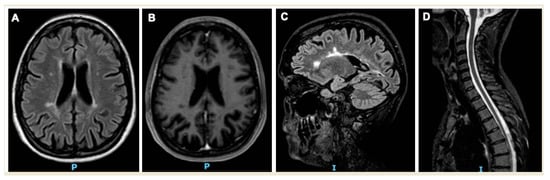

- In 2017, hospitalization for epileptic seizure. In this occasion, she underwent her first MRI that showed inflammatory-demyelinating lesions (reported above).